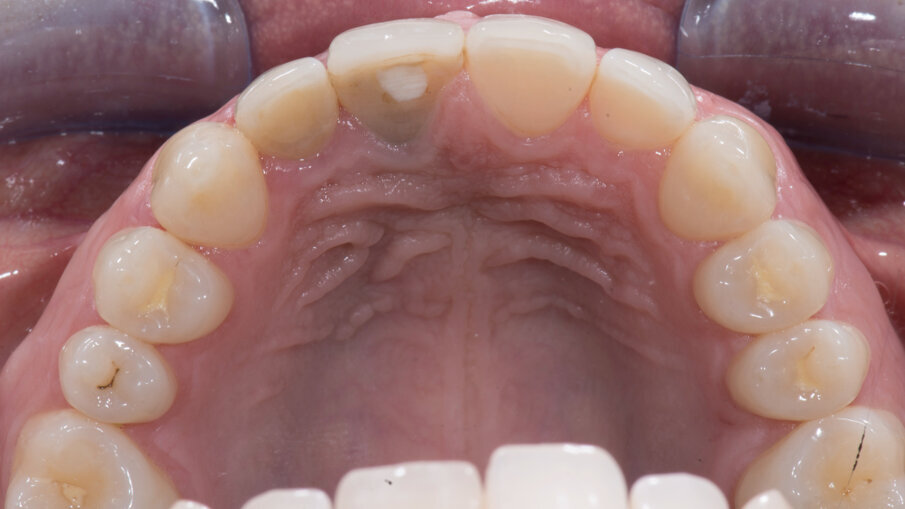

In tutti i casi in cui l’estetica è coinvolta, eseguo sempre lo studio del sorriso seguendo i concetti del “Digital Smile Design” DSD, cercando di ottimizzare l’armonia tra denti del paziente e il suo viso (Fig. 6). In questo caso, dove deve essere gestito un solo elemento dentale, non è necessario ridisegnare completamente tutti i denti dei settori frontali; tuttavia, un approccio estetico ci aiuta a capire quali siano le discrepanze rispetto a una situazione ideale (Fig. 7). Poiché la morfologia del dente 2.1. era congruo sia dal punto di vista proporzionale che armonico rispetto ai denti vicini, mi sono limitato a copiarne la forma riuscendo in tal modo a mantenere i tessuti molli nella posizione originale dopo la fase chirurgica di inserimento di un impianto in posizione 1.1.

- Impronta digitale mediante scanner intraorale

L’aspetto più importante durante questa prima scansione è la creazione della cosiddetta “Maschera Gengivale”, ossia la copiatura dei tessuti molli precedentemente condizionati. Tale scansione, eseguita con Primescan (Dentsply Sirona), ci guiderà durante la fase di progettazione del profilo di emergenza del dente provvisorio. Un corretto profilo d’emergenza rappresenta sicuramente la chiave del successo e ci consentirà di ottenere, in modo predicibile, un buon condizionamento dei tessuti attorno al terzo cervicale del dente avvitato all’impianto. Il modello master superiore deve essere tagliato digitalmente al centro dell’area edentula 1.1 mediante lo strumento “Seziona” (Fig. 10). Dopo la prima impronta digitale, si è proceduto all’estrazione del dente 1.1 (Figg. 11, 12).

Fig. 10_Impronte digitali.